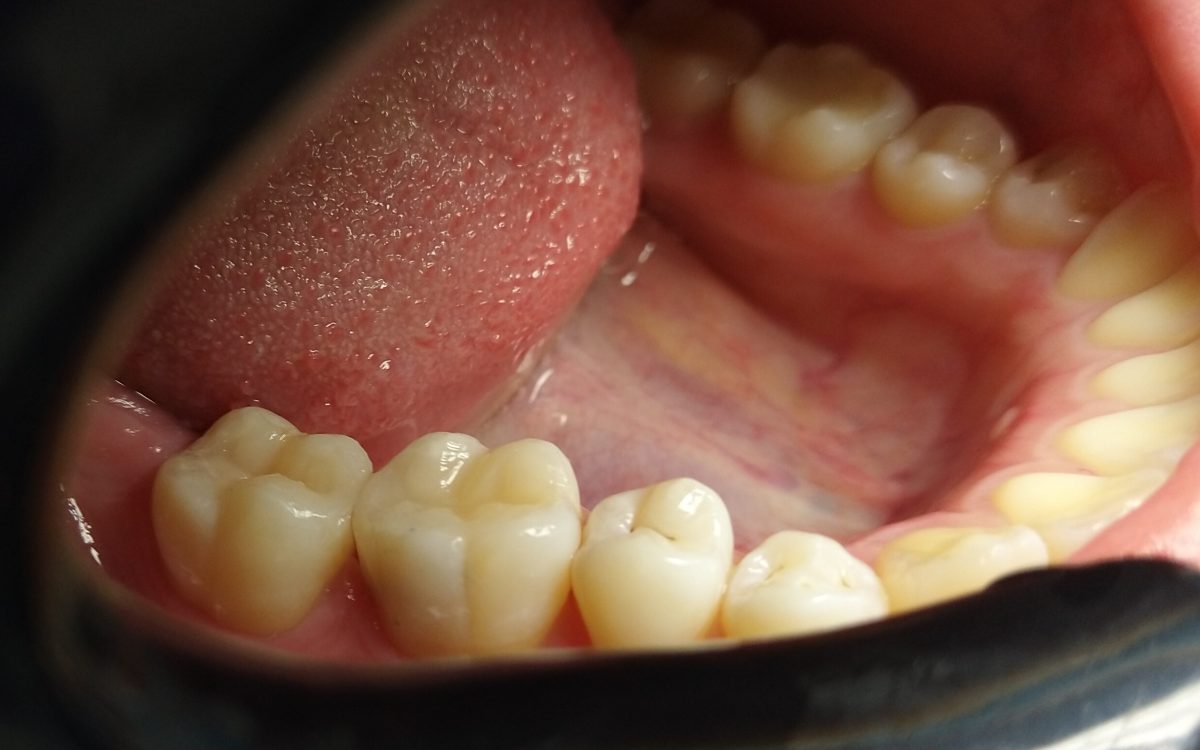

Fog betét

Fog betét (inlay, onlay)

A betét olyan, fogtechnikus által készített esztétikus fogpótlás, mely a fog koronai részén helyezkedik el mint egy nagyobb tömés és bizonyos esetekben nagyobb védelmet képes nyújtani, mint a fogtömés. Betéteket a kis-és nagyőrlő fogakra helyezhetünk! Élethű, strapabíró és megfelelő szájhigiénia mellett sokáig képes védeni a fogat.

Abban az esetben készítjük, amikor a tömés már nem tudná ellátni a fog védelmét.

Ilyen esetek például:

- sok szuvas részt kellett eltávolítanunk a koronai részből

- mély szuvasodás után kezeljük a fogat

- régi, nagy kiterjedésű fogtömést cserélünk

- gyökérkezelt fog koronai részét szeretnénk megóvni

- olyan felületekről kellett foganyagot eltávolítani, ahol az új fogtömés nagy eséllyel letörne harapás közben